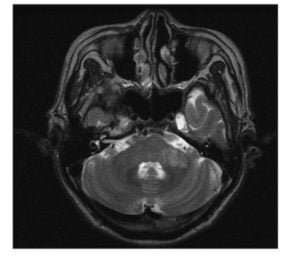

The patient was admitted under neurology and the subsequent MRI on next day reported cerebellar infarction in the territory of AICA . (Fig1)